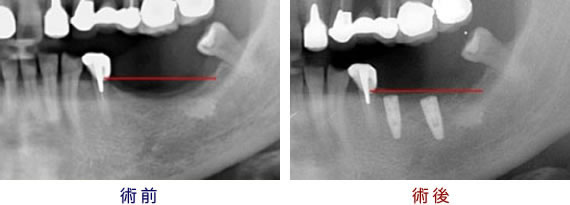

サイナスリフトとは、上顎の奥歯を抜歯したケースによく用いられる再生療法です。上の奥歯が無い場合、時間とともにこの空洞が拡大し、インプラントを埋入するのに十分な上顎の骨の量が足りなく(薄く)なります。 治療法は顎洞側壁骨の相当部の歯ぐきを切開し、骨窓を下から内側に押し上げて上顎洞の粘膜を拳上します。 そして拳上してできたスペースに移植材を入れ、外側を粘膜で被い骨が出来上がるのを待ってからインプラントを埋入します。

上顎の奥歯の骨の高さが不足している場合に用いる骨誘導再生法のことです。

上の奥歯を失ってしまうと、上顎洞が下方に拡大していきます。

同時に、失った歯の周囲の歯槽骨が吸収されていくので、歯槽骨の厚みが加速的に減少していきます。

ソケットリフトとは、そのように上顎の骨の厚みが薄い場合に、厚みを増すために行われる方法です。

上顎洞のインプラントを植える穴(もとの歯が抜けた部分)から、骨のもととなる物質を入れて、 少しずつ上顎洞粘膜(シュナイダー膜)を押し上げていきます。

押し上げられた粘膜と、その間に詰まった骨のもととなる物質の分だけ、骨の厚みを増すことができます。

骨のもととなる物質が固まって、完全に骨になるのを待ってから、インプラントを行います。